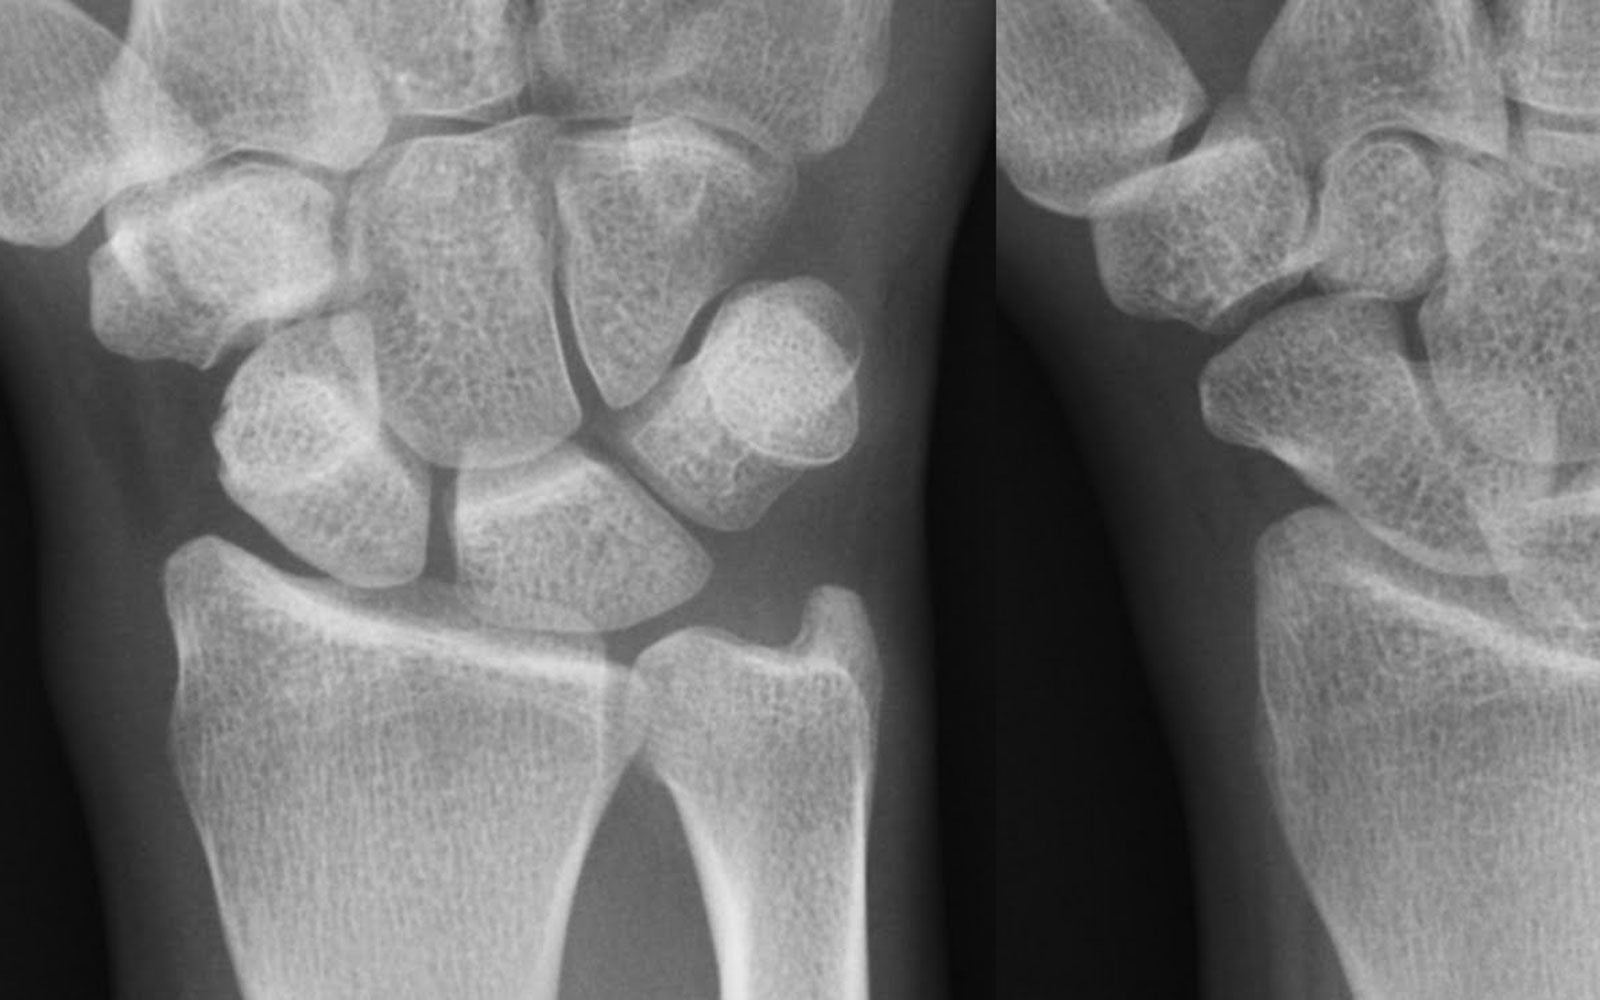

Clinical signs and symptoms: Clients will usually present reporting pain at the radial side of his/her wrist / base of thumb. It is painful with movement of the thumb and / or wrist. The first dorsal wrist compartment is usually tender to palpate over or distal to the radial styloid.

Finkelsteins test: The examiner grasps the client’s hand, places the thumb across the palm and sharply ulnar deviates the wrist. Always compare to the unaffected side. A positive test reproduces their sharp pain at the radial aspect of the wrist / base of thumb.

Observation and palpation: look for swelling / redness / heat (not always present) and palpate for tenderness over the affected tendons at the level of the radial styloid.